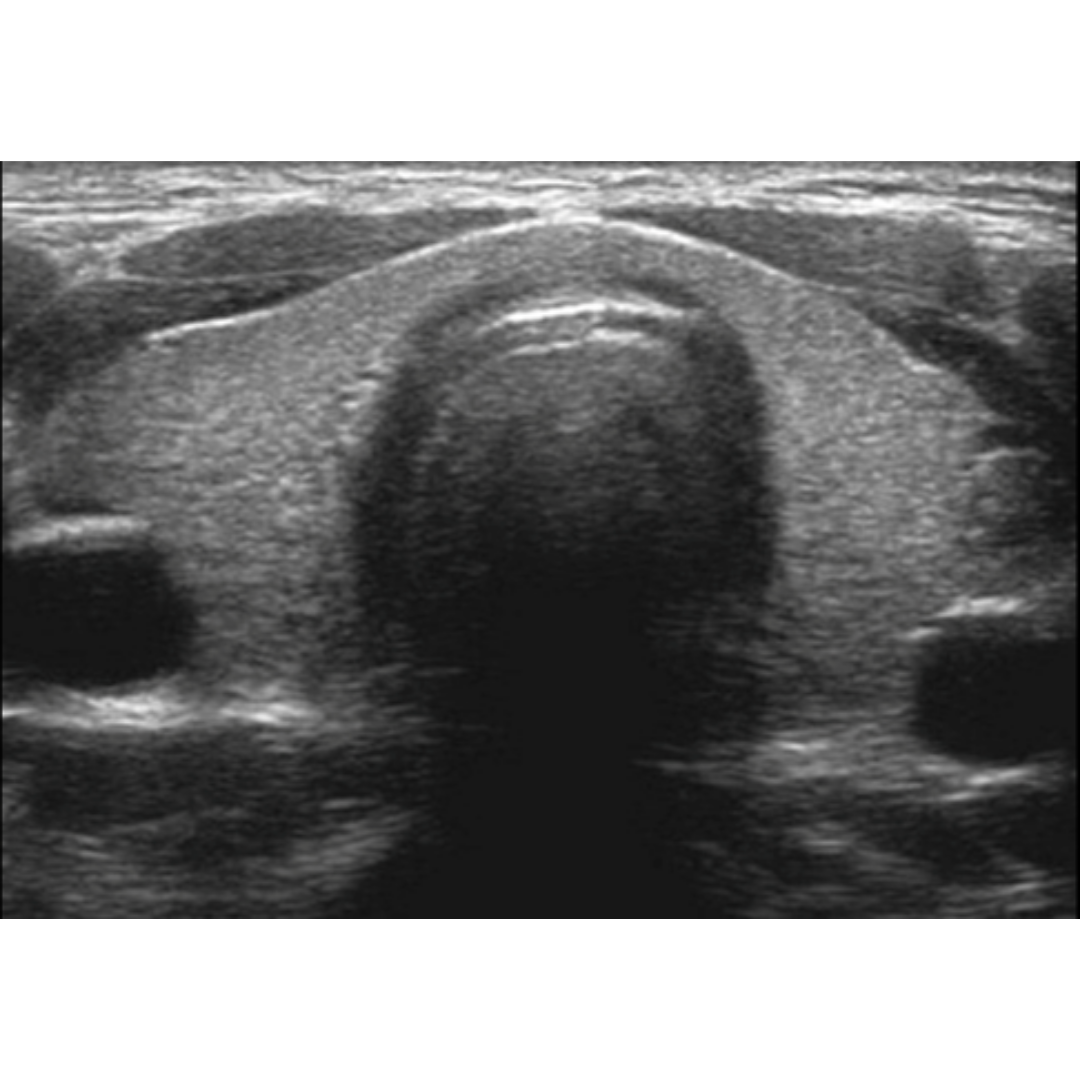

Quiste de Inclusión Epidérmico y sus Características Ecográficas